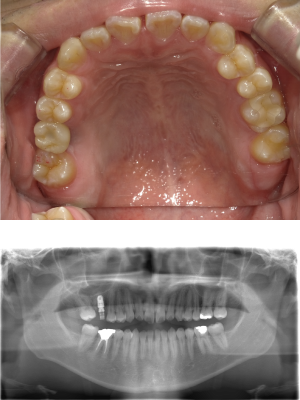

インプラント治療(左上5ソケット・GBR 右上2左上13GBR)

| 年代・性別 | 50代・男性 |

|---|---|

| 主訴 | 入れ歯だと咬めなくてつらい。 |

| 部位 | 上顎②1①2③4⑤Br |

| 治療期間 | 約9ヶ月 |

| 費用 | ¥1,794,100(税込) |

| 副作用・リスク |

|